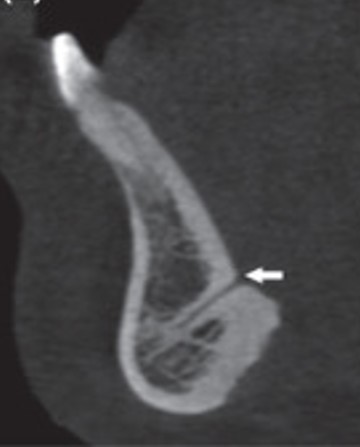

8) Identify the normal anatomic landmark indicated by arrow in the CBCT image below?